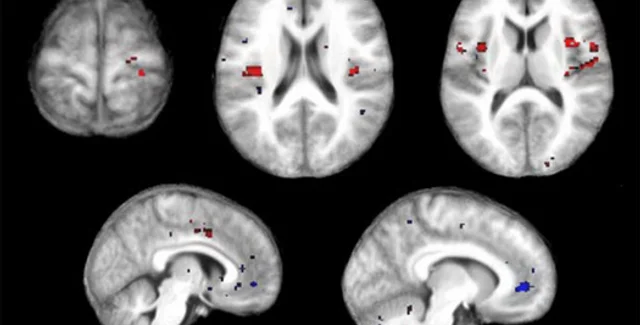

Получить объективные данные о болевых ощущениях ученым позволила комбинация методов Функциональной магнотно-резонансной томографии и особого "самообучающегося" программного алгоритма, сообщает compulenta.ru.

Когда человек что-то видит, слышит и вообще чувствует, у него активируются определенные участки мозга, которые можно обнаружить посредством ФМРТ. Более того, по активности мозга реально предсказать характер ощущений, не зная ничего о том, что именно их вызвало. Информацию о схеме активности можно внести в программный алгоритм, который и будет распознавать ощущения по картинке, сообщаемой ФМРТ.

В эксперименте стэнфордских ученых участвовали восемь добровольцев. Каждому предстояло испытать легкий термический ожог: участок кожи нагревался до тех пор, пока тепловые ощущения не переходили в болевые. Компьютер регистрировал изменения в активности мозга и вычленял общие черты у всех участников эксперимента. После выявления болевого алгоритма исследователи проверили его на 16-ти новых добровольцах, и оказалось, что метод позволяет отличить боль от неболи более чем в 80% случаев.